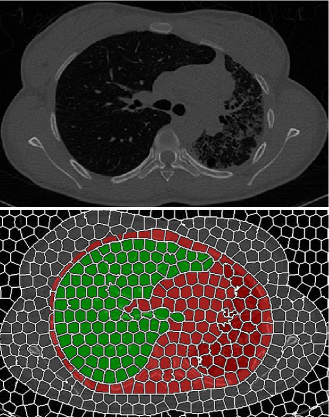

Abnormality detection module consists of two parts. First, a search-space for prospective abnormalities is defined that includes the nearby soft tissue as well as abnormal pulmonary areas that have intensities very similar to nearby soft tissue. The search space is subsequently partitioned into supervoxels by applying an adapted SLIC algorithm to handle gray-scale 3D volumetric CT scans. The algorithm partitions the CT image into superpixels of nearly uniform sizes whose boundaries closely match with the natural boundaries in the image while capturing the redundancy in the data [5]. Supervoxels provide a primitive neighborhood from which a single representative local descriptor can be computed for all voxels belonging to that supervoxel. Finally, the random forest classifier is used for binary classification (pulmonary abnormality, near-by soft tissue) of the descriptors. Fig. 3 summarizes the abnormality segmentation module, the details are presented in the following subsections.

Although local descriptors are very useful for detecting local patterns such as pathologies, it is not trivial to extract discriminative feature sets to drive the detection process. Moreover, assessing every voxel’s class label may be computationally expensive. To address these two challenges, we integrated rib cage extraction and convex-hull fitting processes into the random forest classification algorithm in order to restrict the search space (Fig. 4) to rib cage area only. To further reduce the redundancy, the local descriptors are calculated only at the centroid of the supervoxels (Fig. 5) within the search space forming an optimized keypoint sampling grid since the centroid of texturally uniform supervoxel can be assumed to representative of the entire supervoxel. For random forest voxel classification of lung tissues, we employ grey-level run length matrix (GLRLM), gray-level co-occurrence matrix (GLCM), and histogram features. Justification of the use of GLCM, GLRLM, and histogram features is based on the visual analysis of CT lung pathologies [6].